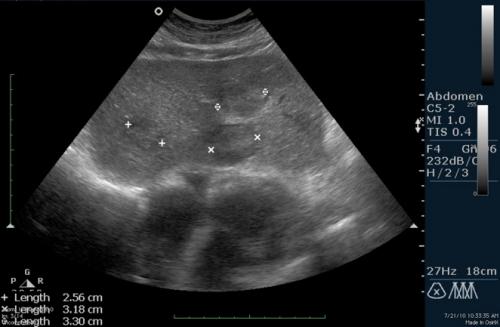

Диагностировать опухоль в поджелудочной железе можно с помощью:

- УЗИ. Лучше всего эндоскопическое, через желудок или двенадцатиперстную кишку. Поможет выявить рак маленьких размеров;